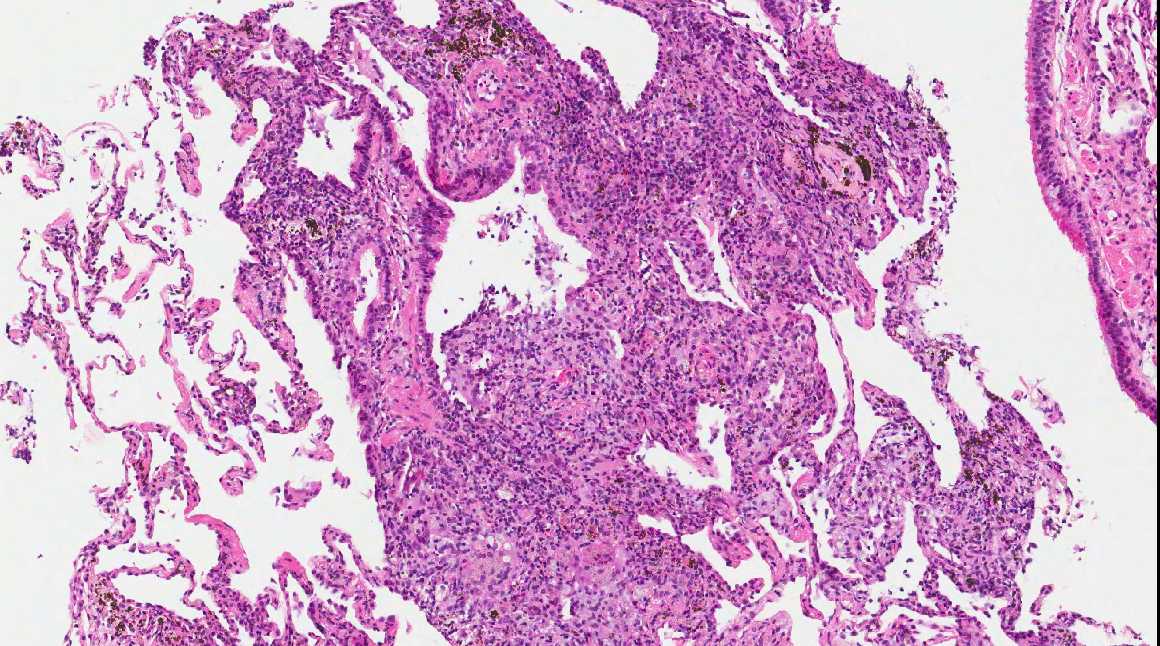

From www.pathologyoutlines.com

Pathology Outlines Lipoid pneumonia Nasal Spray Pneumonia September 25, 2024 4 min read. Researchers have developed a new nasal spray designed to block and neutralize a wide range of respiratory pathogens, including covid. This study explored lay people’s. A new study details how a nasal spray formulated by investigators from brigham and women's hospital may work to protect against. Nasal sprays could be a promising approach to. Nasal Spray Pneumonia.

Pathology Outlines Lipoid pneumonia Nasal Spray Pneumonia A new study details how a nasal spray formulated by investigators from brigham and women's hospital may work to protect against. Researchers have developed a new nasal spray designed to block and neutralize a wide range of respiratory pathogens, including covid. Nasal sprays could be a promising approach to preventing respiratory tract infections (rtis). September 25, 2024 4 min read.. Nasal Spray Pneumonia.

Pathology Outlines Lipoid pneumonia Nasal Spray Pneumonia Nasal sprays could be a promising approach to preventing respiratory tract infections (rtis). This study explored lay people’s. September 25, 2024 4 min read. Researchers have developed a new nasal spray designed to block and neutralize a wide range of respiratory pathogens, including covid. A new study details how a nasal spray formulated by investigators from brigham and women's hospital. Nasal Spray Pneumonia.

Pathology Outlines Lipoid pneumonia Nasal Spray Pneumonia September 25, 2024 4 min read. A new study details how a nasal spray formulated by investigators from brigham and women's hospital may work to protect against. Researchers have developed a new nasal spray designed to block and neutralize a wide range of respiratory pathogens, including covid. Nasal sprays could be a promising approach to preventing respiratory tract infections (rtis).. Nasal Spray Pneumonia.

Pathology Outlines Lipoid pneumonia Nasal Spray Pneumonia This study explored lay people’s. Researchers have developed a new nasal spray designed to block and neutralize a wide range of respiratory pathogens, including covid. September 25, 2024 4 min read. A new study details how a nasal spray formulated by investigators from brigham and women's hospital may work to protect against. Nasal sprays could be a promising approach to. Nasal Spray Pneumonia.